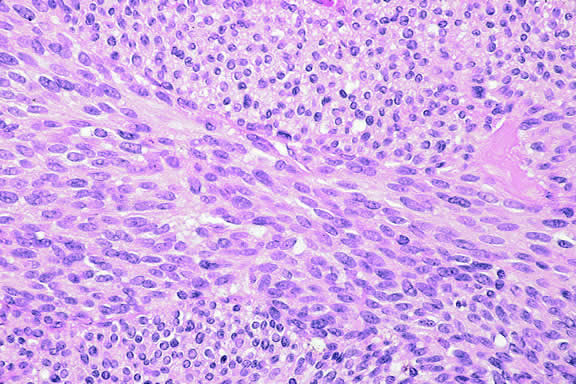

Histopathology

The cells comprising uveal melanoma constitute a biologic spectrum comprising bland spindle A melanoma cells at one end and wildly anaplastic epithelioid cells at the other. The term spindle cell is derived from the fusiform or spindled configuration of the cells' cytoplasmic outline. They are bipolar in shape, and many have long tapering processes that occasionally are highlighted when individual pigmented cells are seen in a largely amelanotic tumor. Spindle cells grow in a syncytial fashion forming interweaving fascicles of parallel oriented cells (Fig. 30). The cells can be pigmented or nonpigmented. Two types of spindle cells are recognized; spindle A and spindle B. These are distinguished by their nuclear characteristics. Spindle A nuclei are tapering ovals or cigar-shaped and have finely dispersed chromatin (Fig. 31). If a nucleolus is present, it usually is inconspicuous. Many spindle A cells have a longitudinally oriented chromatin stripe that actually is caused by a fold in the nuclear membrane. The nuclei of spindle B cells have distinct nucleoli and coarser chromatin and tend to be plumper and more oval in shape (Fig. 32).

Fig. 30. Amelanotic spindle cell melanoma. Tumor is composed of interweaving fascicles of spindle cells. Photomicrograph shows longitudinally and transversely sectioned fascicles. (Hematoxylin-eosin, × 100.)